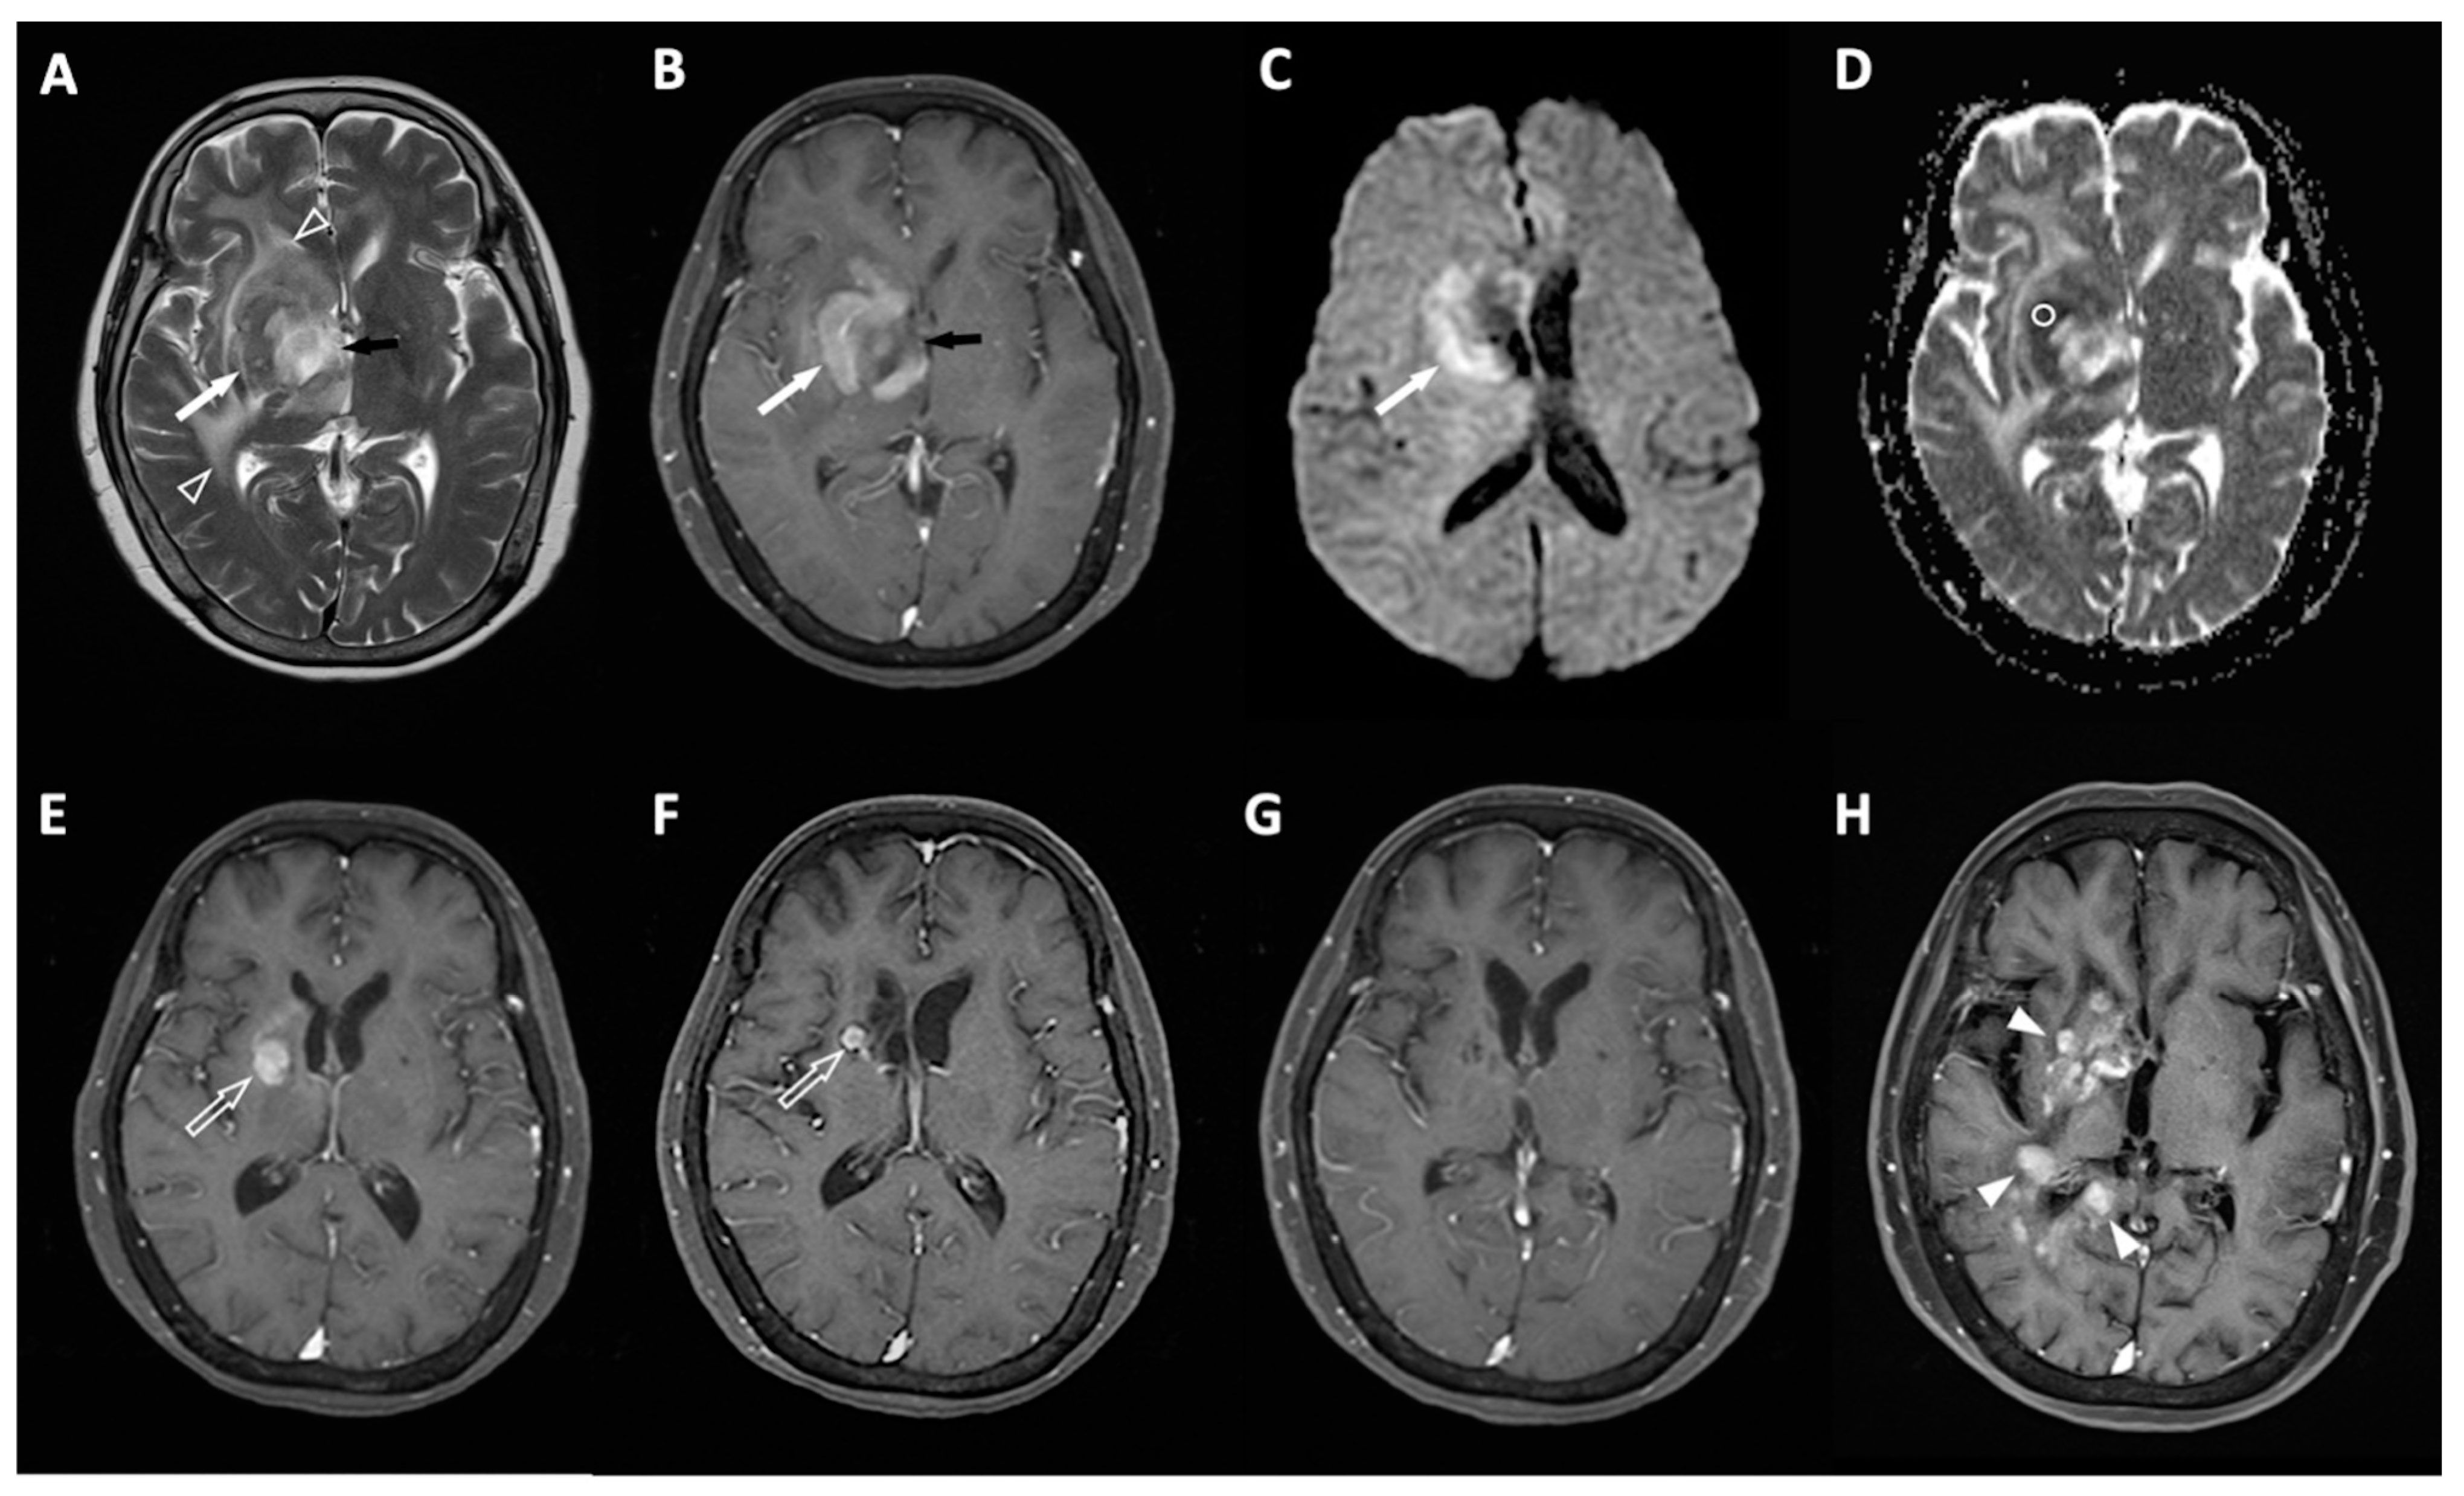

4.1. Clinical Information and MRI Results